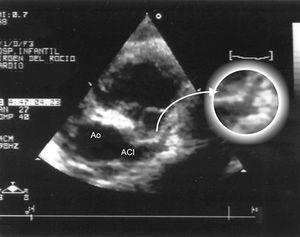

A los 10 días de vida presentó bruscamente disnea por edema pulmonar, cardiomegalia, hipotensión arterial y oliguria. En sus electrocardiogramas (ECG) se apreciaban voltajes muy atenuados de los complejos, y en la ecocardiografía, una gran dilatación de cavidades izquierdas (DdVI: 38 mm) con insuficiencia mitral moderada y gravísima afectación de la contractilidad (fig. 1). El cuadro era compatible con miocarditis aguda grave.

Figura 1. Dilatación de cavidades izquierdas (10 días de vida): A) Ecocardiografía 2D, proyección paraesternal de eje largo: enorme dilatación de la aurícula izquierda: relación AI/Ao 3.B) Ecocardiografía modo M del ventrículo izquierdo (10 días): dilatación del ventrículo izquierdo con importante afectación de su contractilidad; AF: 18,5; FE: 35,5 %.